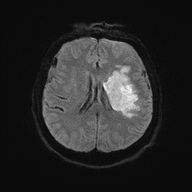

| T2 FLAIR | T2 |

|---|---|

![]() |

| FLAIR | Edema, gliosis, demyelination near CSF spaces | CSF (suppressed), normal fluid | MS, periventricular lesions, subarachnoid space pathologies |